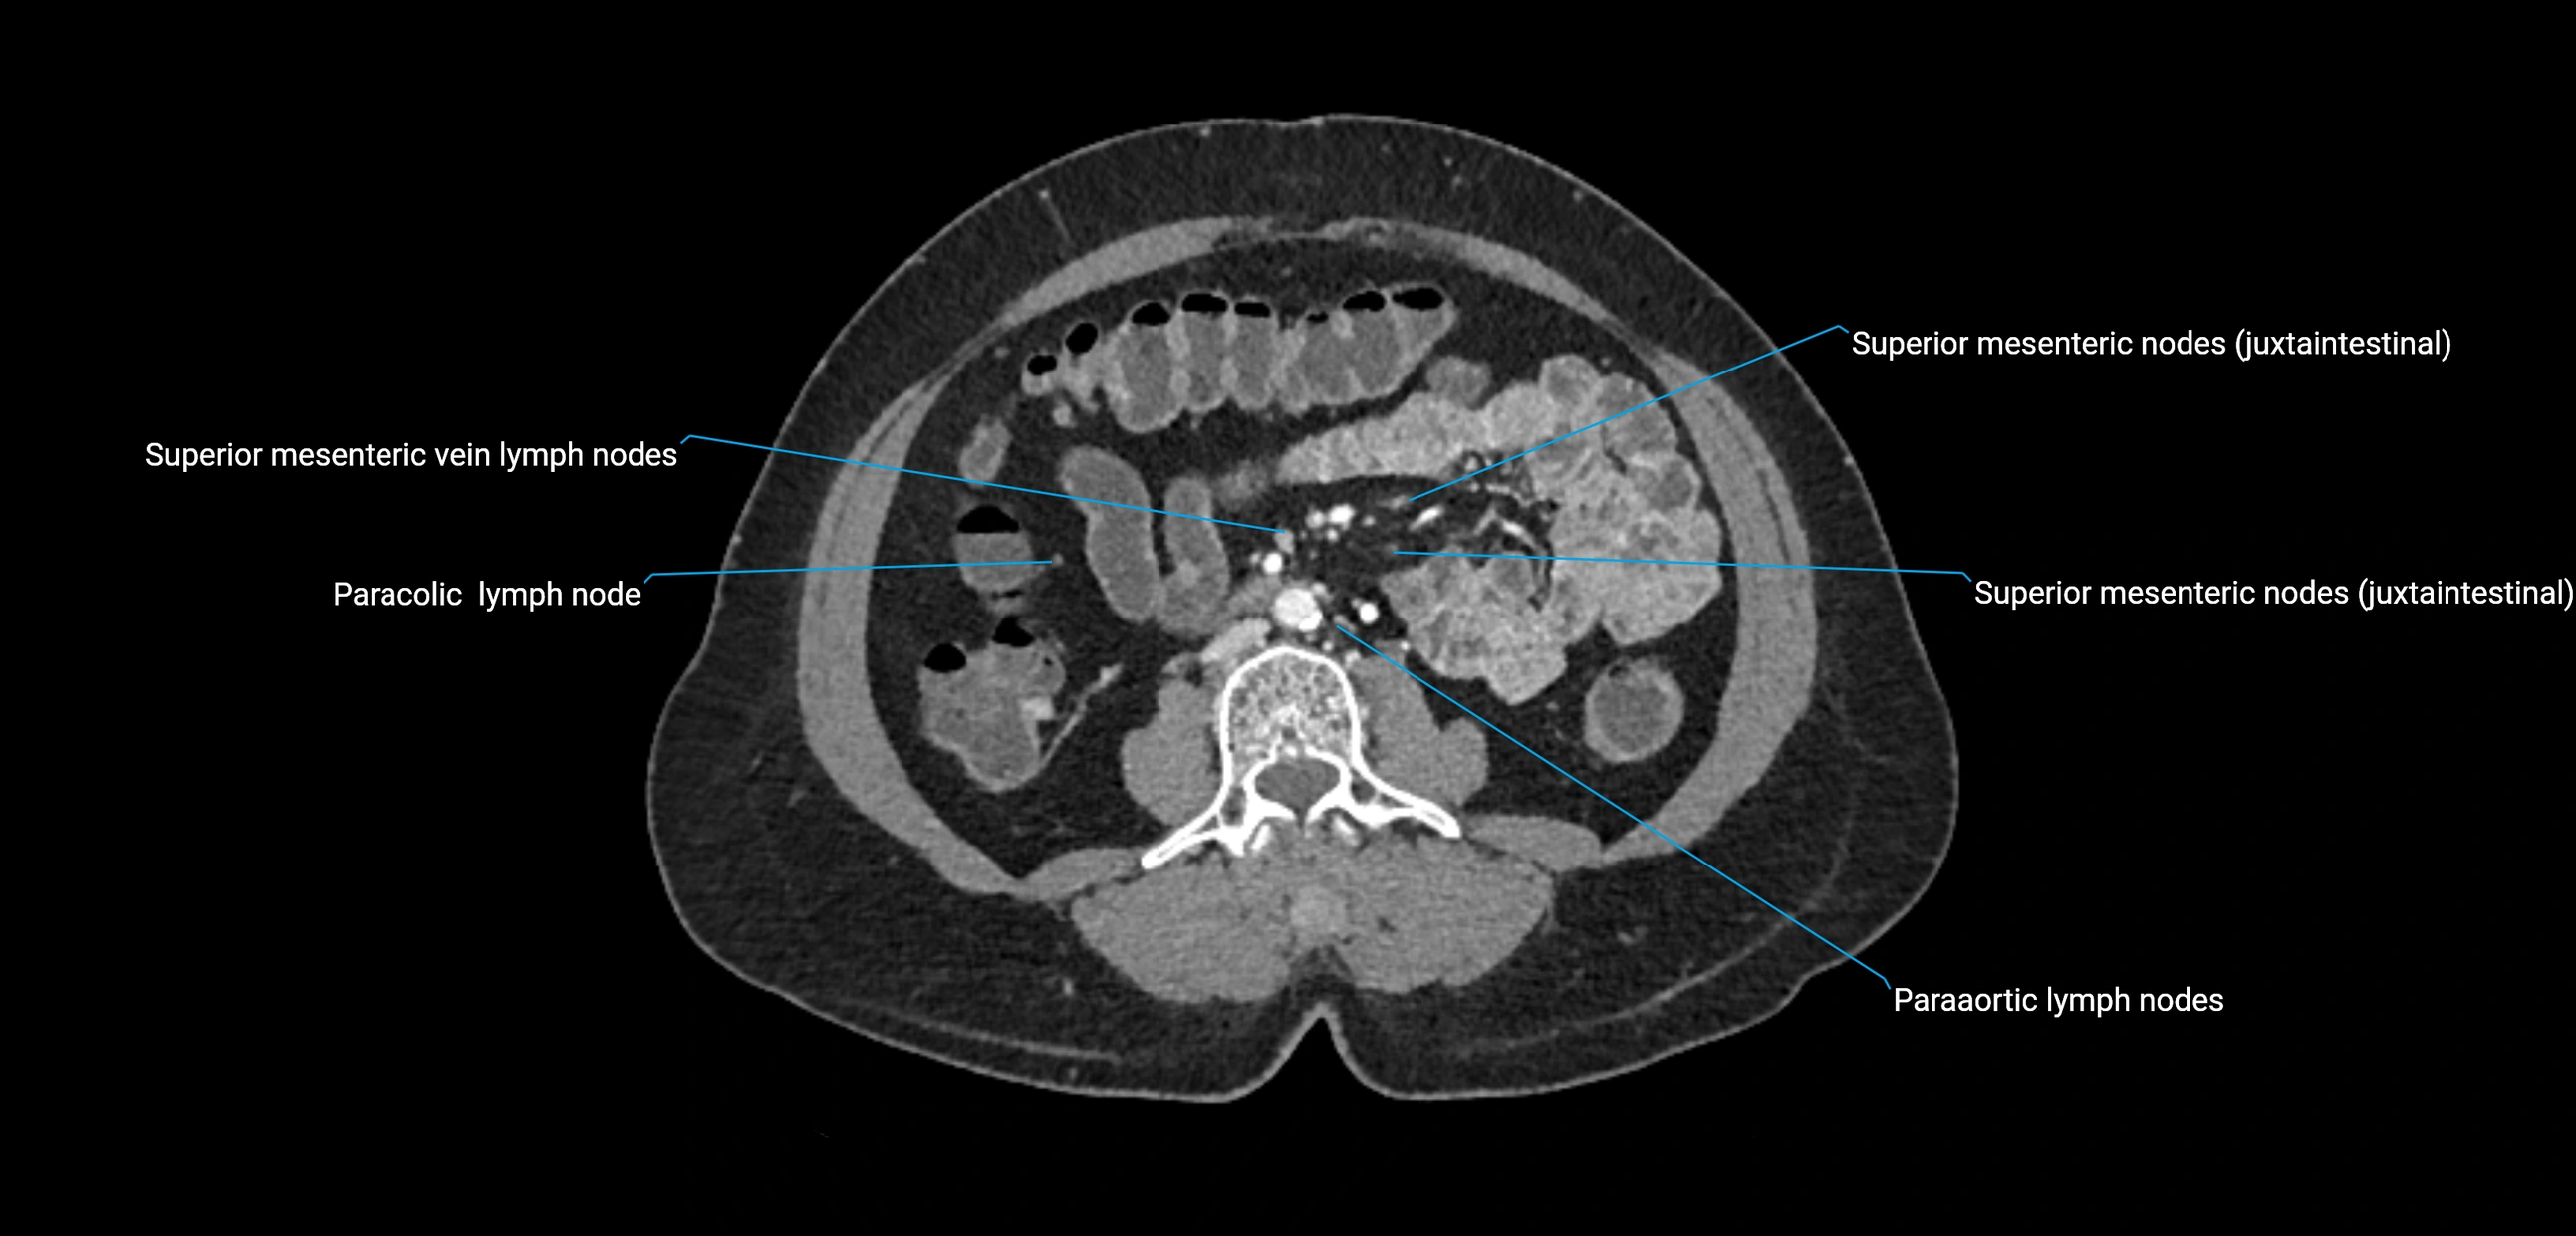

CT Appearance

CT Pre-Contrast:

• Nodes appear as soft-tissue density nodules adjacent to the aorta and IVC

• Calcification may be seen in chronic infections (e.g., tuberculosis)

CT Post-Contrast:

• Normal nodes enhance homogeneously

• Malignant nodes may show heterogeneous enhancement, central necrosis, or conglomerate formation

• Size >1 cm short axis is suspicious, though morphology and distribution are equally important

CT Venography (CTV):

• Demonstrates nodal encasement or compression of adjacent vessels (aorta, IVC, renal veins)

• Useful in staging testicular and ovarian malignancies

• Provides 3D reconstructions for retroperitoneal lymph node dissection planning